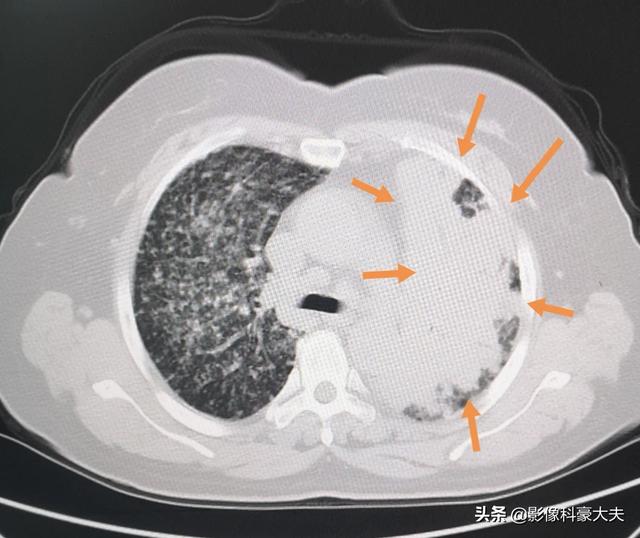

今日も女性の患者さんで、食わず嫌いのためバリウム食で胃の状態をチェックし、その結果、透視検査で肺に影が伸びているのが見つかり、続いて胸部CTで広範囲に転移がある進行肺癌と診断された.